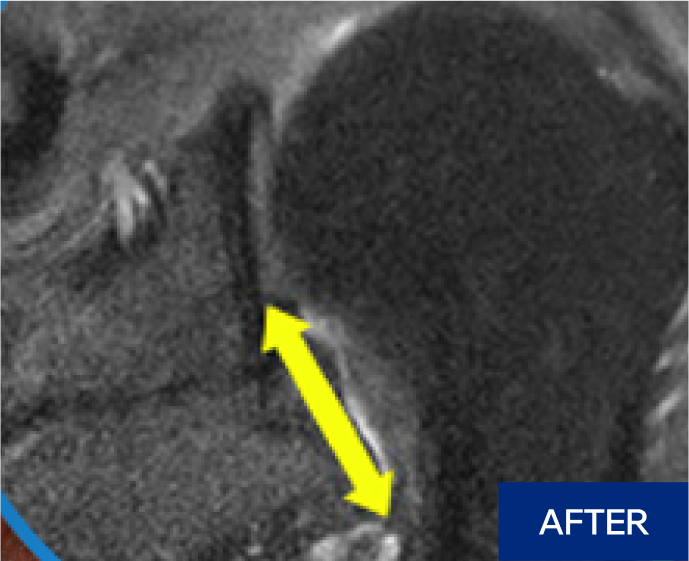

수술 상처 없이 간단한 시술로 관절막을 열어줍니다.

마취 후 전문 의료진이

어깨를 6방향으로

움직여 유착 해소

5~20분 소요

무절개, 빠른 회복

시술 중, 시술 후

빠른 통증 경감과

운동 범위 회복